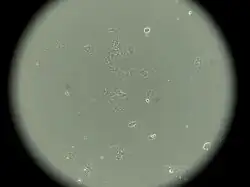

MCF-7 est le nom de la lignée de cellules tumorales mammaires la plus utilisée dans les laboratoires de recherche sur le cancer du sein. Ainsi, elle est mentionnée dans plus d'un tiers des articles scientifiques rapportant des travaux sur des lignées tumorales mammaires (voir PubMed). Avec deux autres lignées courantes, appelées T-47D et MDA-MB-231, elle représente les deux-tiers de ces articles[1]. MCF-7 est l'acronyme de Michigan Cancer Foundation - 7, en référence à l'institut de Detroit où la lignée fut établie -au septième essai-, en 1973, par Herbert Soule et collègues[2].

La lignée MCF-7 a été établie en culture in vitro à partir d'un épanchement pleural prélevé chez une patiente de 69 ans atteinte d'un cancer du sein métastatique. Cette patiente, dont le nom est ignoré de l'immense majorité des chercheurs en cancérologie, est décédée en 1970. Ses cellules ont été à l'origine d'une bonne partie des connaissances actuelles sur le cancer du sein[2],[3]. Elle s'appelait Frances Mallon, et était, à l'époque du prélèvement, religieuse au couvent du Cœur Immaculé de Marie (Immaculate Heart of Mary Convent, Monroe, Michigan), sous le nom de sœur Catherine Frances.